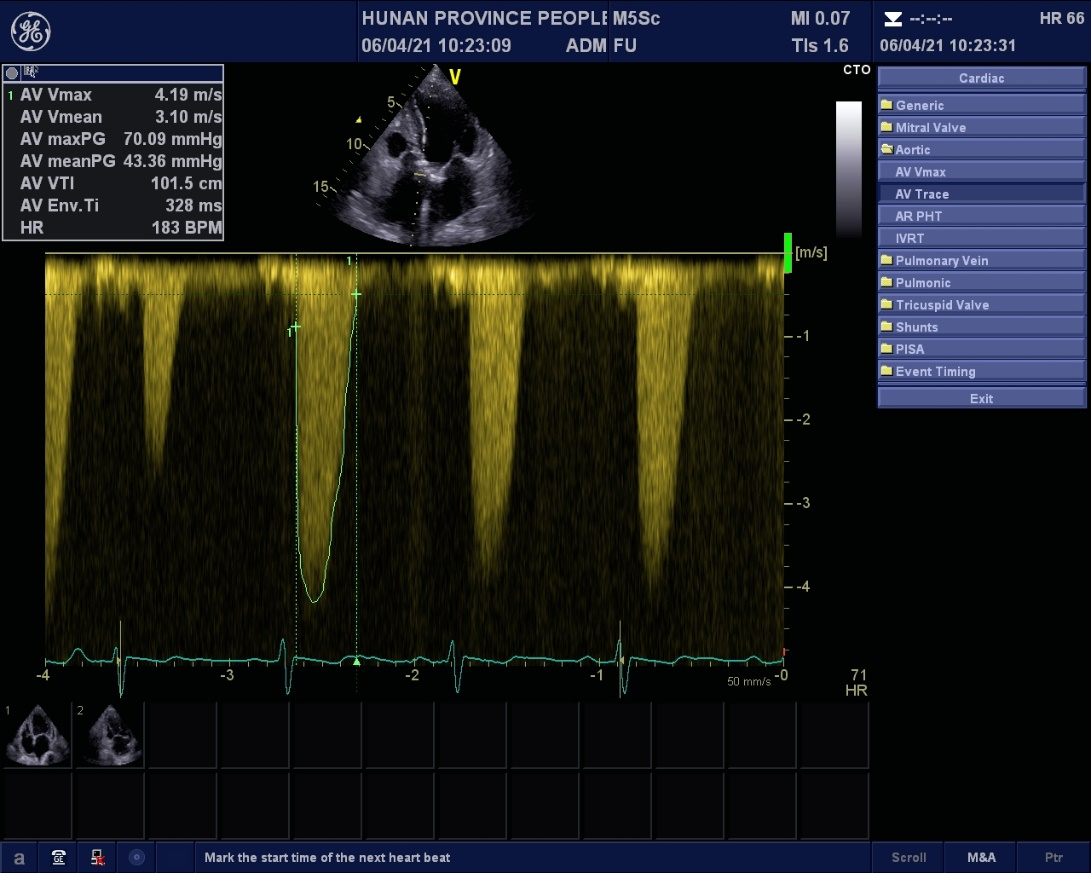

杨嗲嗲既往有“肺气肿”、“颈动脉粥样硬化”、 “胆囊结石”、 “前列腺增生”等病史。心脏彩超显示主动脉瓣钙化、重度狭窄并返流,冠脉影像显示冠状动脉病变也很严重。